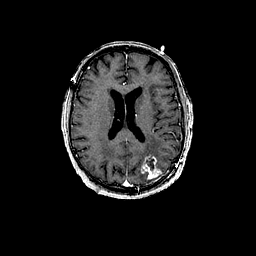

Glioma overlay -- Slice #70

[Home][Help][Clinical] Slice 70